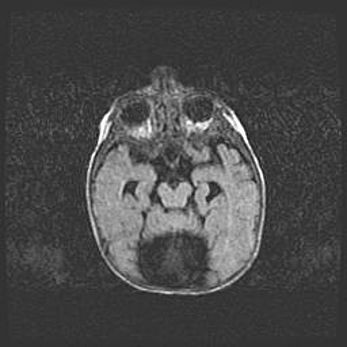

Неполная лизэнцефалия (пахигирия). Открытая гидроцефалия.

Возраст: 17 дней

Вес: 3110 г

Пол: мужской

Окружность головы: 33,5 см

Срок гестации: 35-36 недель

Лизэнцефалия—недоразвитие корковой пластинки и мозговых извилин в результате нарушения миграции нейронов коры. Поверхность мозговых полушарий гладкая. Микроскопически выявляется отсутствие нормальных слоев коры и скопление групп нейронов в подкорковом белом веществе.

Пахигирия—уменьшение числа вторичных извилин. В пораженном полушарии нервные клетки образуют толстый недифференцированный слой с неправильно расположенными нервными волокнами и группами гетеротопных клеток. Нервные клетки незрелые. Белое вещество истончено. При этом нередко аномально развит корково-спинномозговой путь.